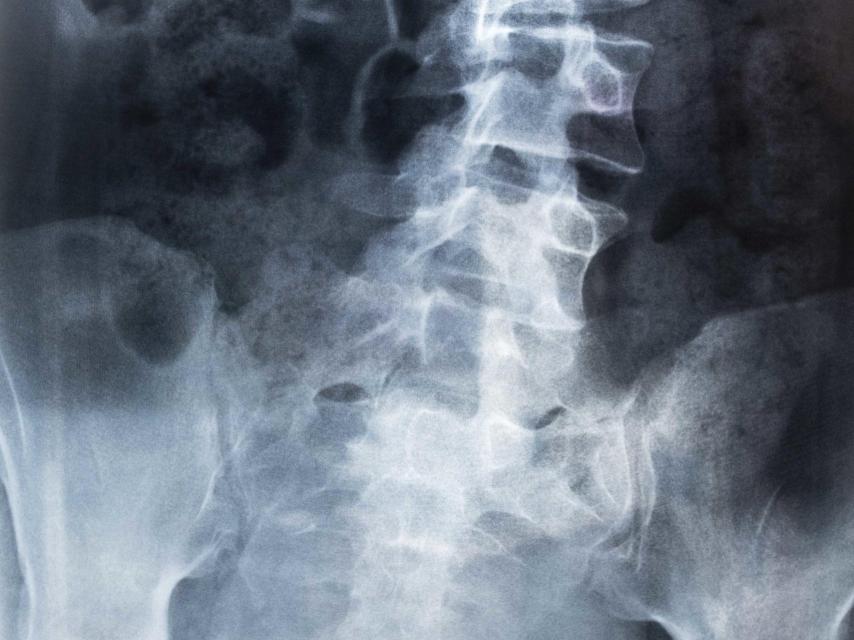

Popovici, de gran altura, actualmente se encuentra cerca ya de los 2 metros, padece problemas de espalda desde que era muy pequeño. Los médicos, tras muchos exámenes, determinaron que padecía escoliosis, una curvatura anómala de la columna vertebral que en ocasiones puede producirse en forma de S y otras veces en forma de C.

Radiografía de una espalda con escoliosis

Generalmente, su origen es congénito, causada por anomalías en las vértebras presentes ya en el nacimiento, aunque su mayor fase de desarrollo se produce en la infancia y la adolescencia. Para combatir estos problemas, los médicos que trataron a Davide cuando todavía era un niño, más de lo que lo es ahora, le indicaron que nadar podría ser una buena terapia para su lesión. Y se lanzó a una piscina que le abrió un camino nuevo en su vida.